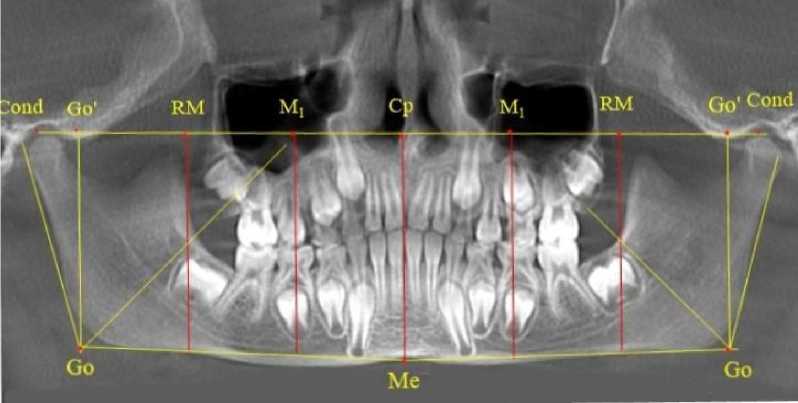

Особенностью исследуемого возрастного периода было то, что зачатки вторых верхних постоянных моляров располагались впереди ретромолярной вертикали. Данное обстоятельство свидетельствовало о благоприятном расположении зачатков, что в последующем обеспечивало их прорезывание по мере формирования корней. Кроме того, указанный размер (Ср-RM) определял зубоальвеолярный размер верхней челюсти (правой и левой). Молярная вертикаль исходящая из молярной токи (М1), в отличие от периода молочного прикуса, смещалась к средней трети медиальной поверхности вторых молочных моляров обеих челюстей, что связано увеличением ретромолярной области (рис. 5).

Рис. 5. Ортопантомограмма ребенка 7 лет после прорезывания первой группы постоянных зубов

Зачатки вторых постоянных моляров нижней челюсти располагались кпереди по отношению к биссектрисе угла Go´-Go-Ме, что так же, как и на верхней челюсти, оказывало благоприятное влияние на формирование и прорезывание нижнего первого моляра. При анализе боковых телерентгенограмм и трехмерной модели установлено, что положение зубов и челюстей относительно реперных линий было близким по значениям, полученным при анализе ортопантомограмм. Биссектриса угла Cond-Go-Ме, так же, как и на ортопантомограмме, располагались позади от формирующихся зачатков вторых постоянных моляров нижней челюсти (рис. 6).

При анализе рентгенограмм детей, у которых прорезались постоянные резцы (вторая группа прорезывания), отмечено, что зачатки вторых верхних постоянных моляров, так же, как и у детей предыдущей группы, располагались впереди ретромолярной вертикали.

Данное обстоятельство свидетельствовало о благоприятном расположении зачатков. Молярная вертикаль, исходящая из молярной токи ( М 1 ) проходила вблизи средней части коронок вторых молочных моляров обеих челюстей (рис. 7).

После полного замещения молочных зубов постоянными продолжалась минерализация и формирование корней постоянных премоляров, клыков и вторых моляров. Зачатки формирующихся вторых верхних постоянных моляров, так же, как и у детей предыдущей группы, располагались впереди ретро молярной вертикали (рис. 9).

Рис. 7. Ортопантомограмма ребенка 8 лет после прорезывания постоянных резцов

Рис. 9. Рентгенограмма ребенка 12 лет после замещения молочных зубов постоянными